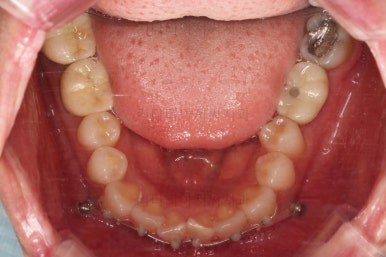

아랫니는 일반 브라켓 보다 매우 작은 장치가 들어갔는데요.

미니튜브 장치에요.

일반적으로 MTA 장치라고 많이 알려져 있는데요. MTA라는 상품명과는 다른 장치이긴한데 왜 이 장치를 사용했을까요?

보기도 덜 보이는 장점이 있지만 이번 환자분의 경우에는 아랫니가 약간 솟구쳐 오르면서 장치를 부착하게 되면 씹혀서 매우 불편감이 예상되었었어요.

그래서 초기 정렬단계에서는 미니튜브를 이용해 주고, 추후에 좀 더 정교한 조절이 필요한 상황에서는 브라켓장치(엠파워 클리어)로 재부착하기로 했어요.

그리고 아랫니 송고니 옆 잇몸에 보시면 미니스크류가 식립이 되어있는데요.

이는 솟구친 아래 앞니의 높이를 조절하기 위해 사용이 됩니다.

이부분이 해결이 되어야 좀 더 완성도 높은 부분교정이 가능해요.